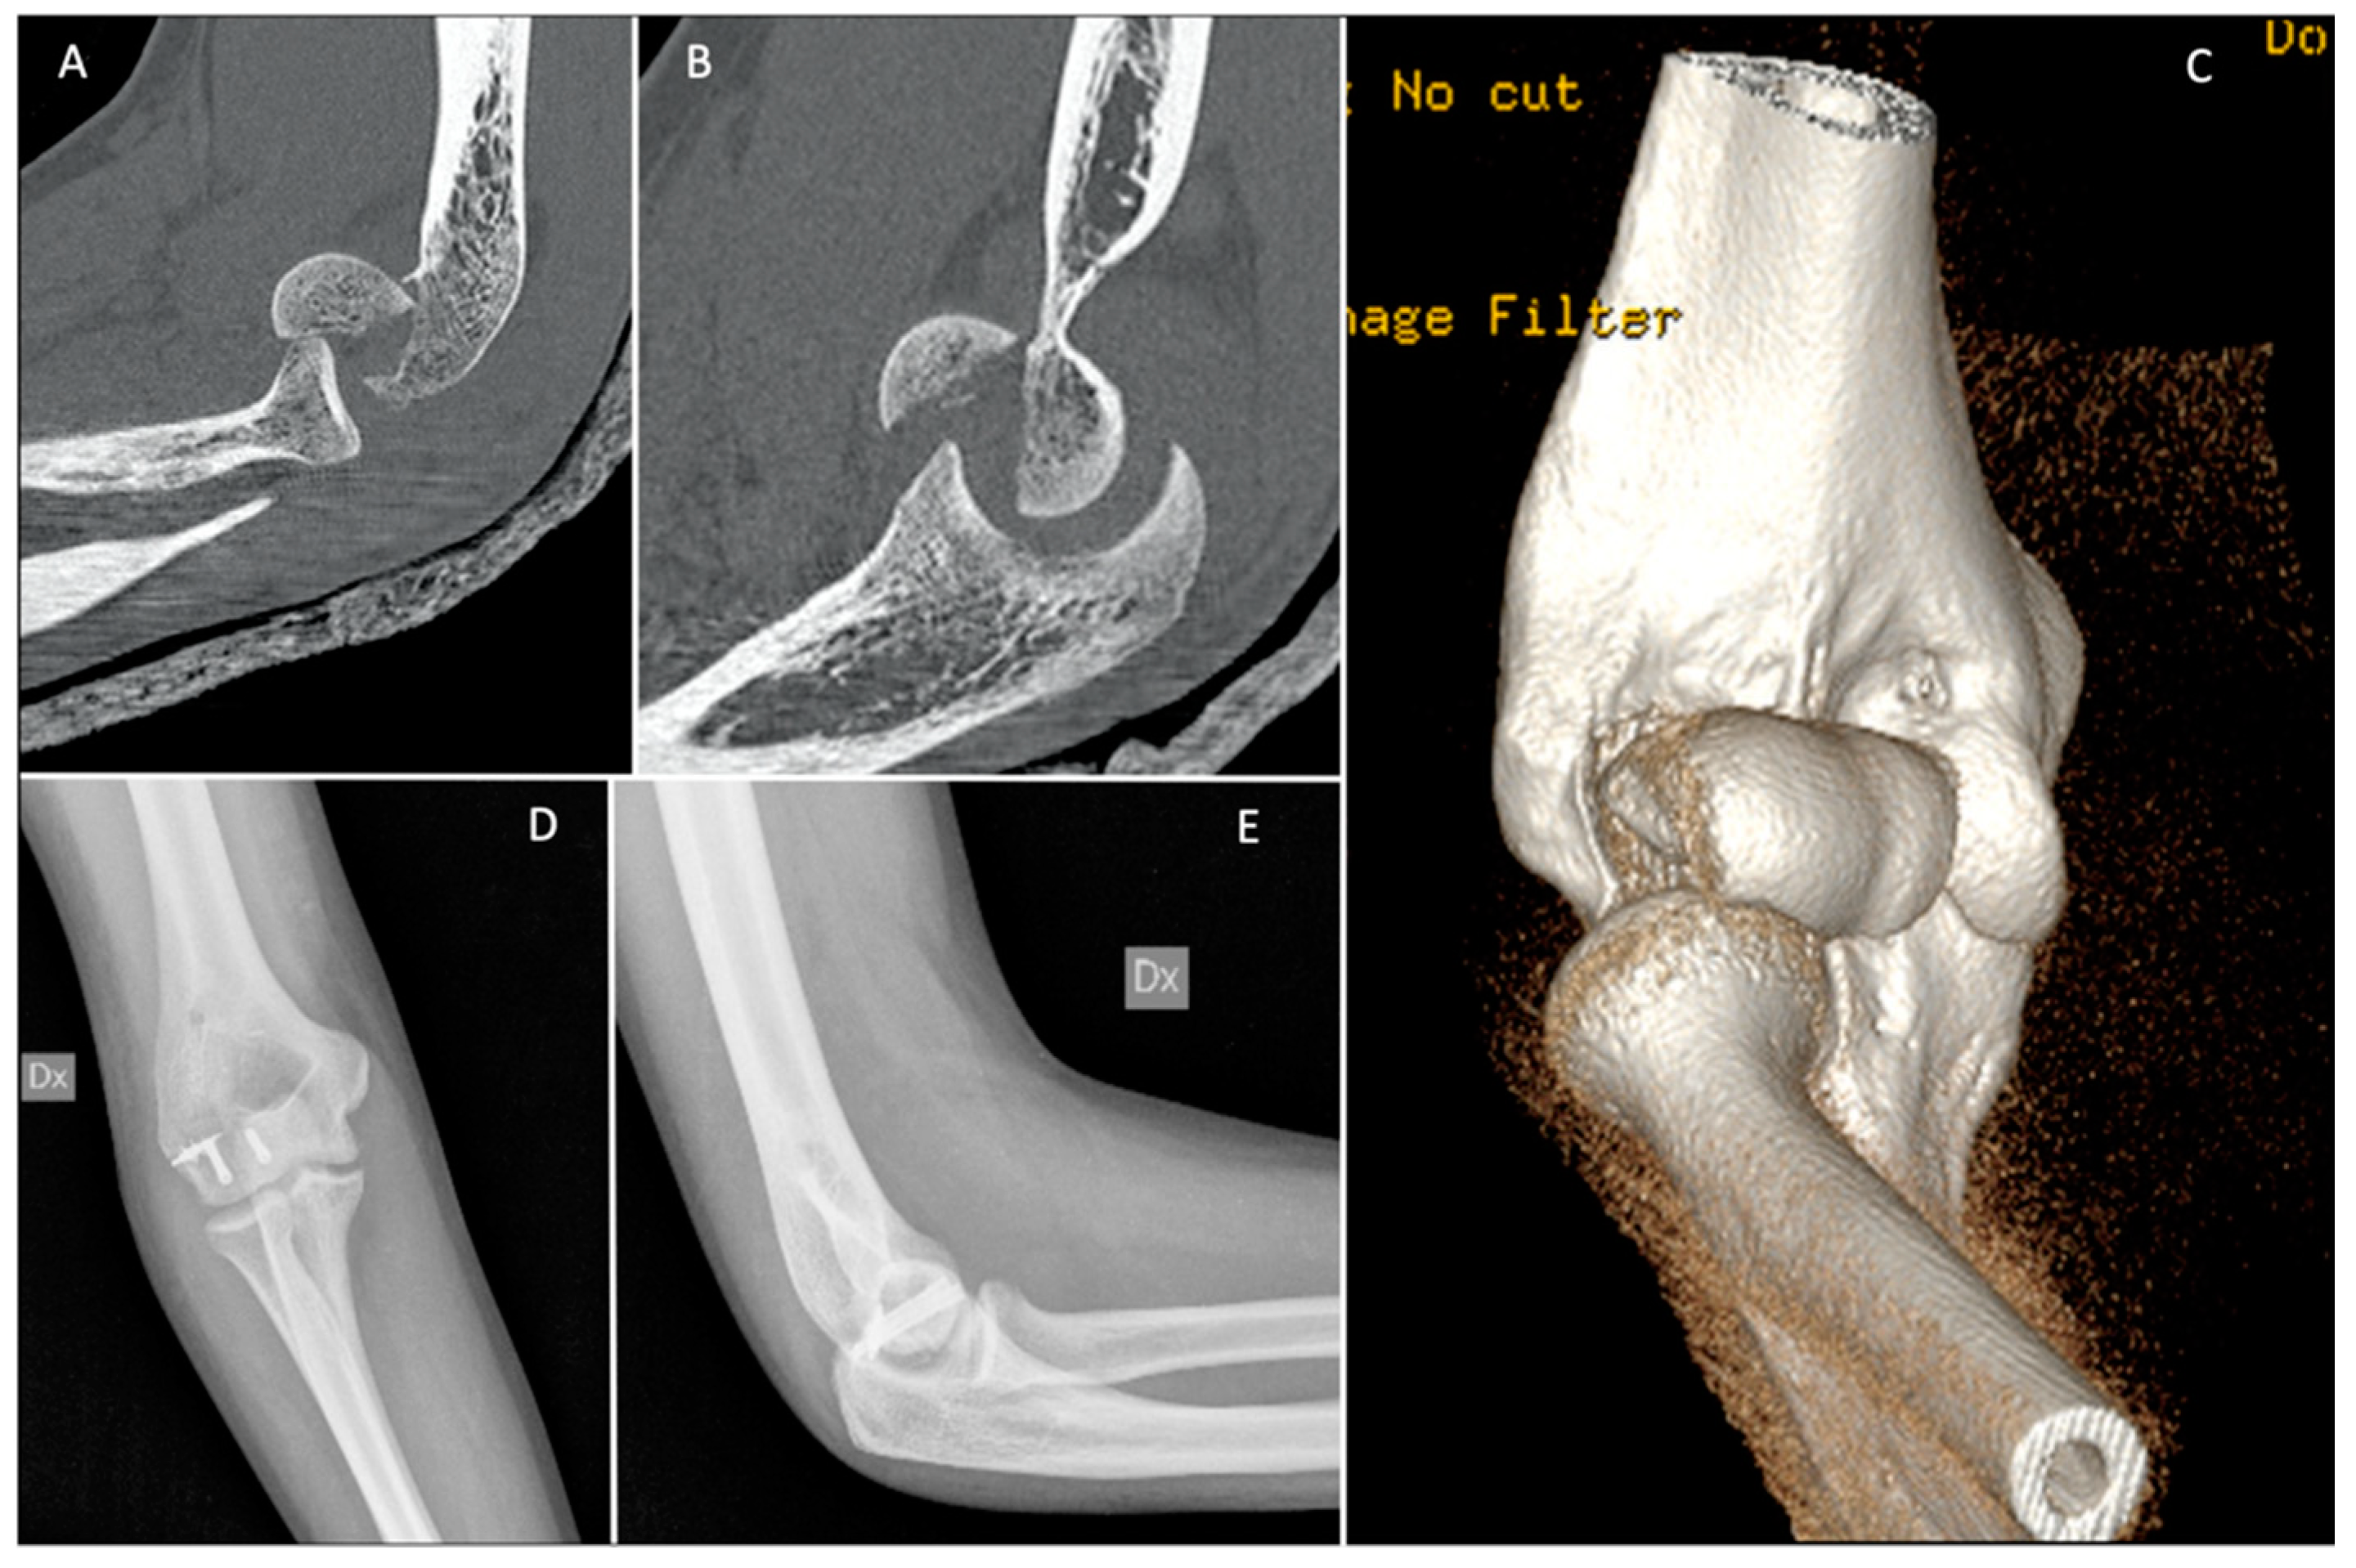

2. Classification

3. Imaging

4.1. Planning